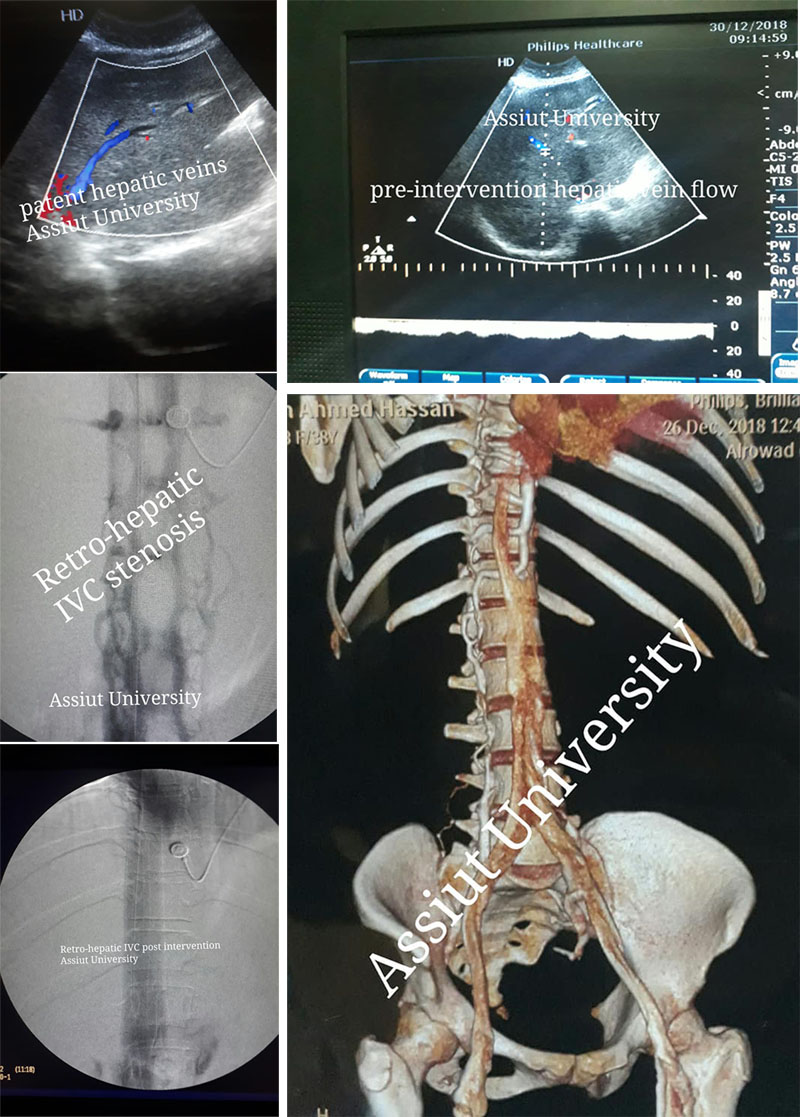

تتويجاً لنجاحات قسم جراحة الأوعية الدموية الممتدة لجيله المؤسس الأستاذ الدكتور/ حسن بكر البدوي والأستاذ الدكتور/ بهجت عبد الحميد و الأستاذ الدكتور/ محمد علاء مبارك، وبرعاية رئيس القسم الأستاذ الدكتور/ مصطفي سعد.

قام فريق طبي من القسم مكون من الدكتور/ هشام أبو العيون مدرس جراحة الأوعية و الدكتور/ أشرف النجار مدرس جراحة الأوعية و الدكتور/ عثمان محمود أحمد مدرس جراحة الأوعية بعمل قسطرة وتوسيع بالبالون وتركيب دعامتين لضيق شديد بالوريد الأجوف السفلى خلف وأعلى الكبد

Budd chairi syndrome due to IVC stenosis retro and suprahepatic

مدعومة لإستخدام قسطرة الايفوس والتي تمثل أحدث وأدق قسطرة لقياس نسبة الضيق وطوله وتحديد المكان المناسب لوضع الدعامات.

وقام الفريق برعاية أ.د/ بهجت عبد الحميد ثابت و أ.د/ خالد عبد العزيز و أ.د/ أشرف جمال طه بالتخطيط لعلاج حاله تبلغ من العمر 38 عام تعانى من تضخم بالكبد والطحال وإستسقاء بالبطن ناتج عن ضيق شديد بالوريد الأجوف خلف وأعلى الكبد و التي تم تشخيصها في تعاون مع فريق قسم الجراحة العامة ط/ نجم الدين بعد أن كانت تعانى منذ عام ونصف من آلام وإنتفاخ بالبطن ولم يتم تشخيصها

وعند مناظرة الحالة بالمستشفى الجامعي وإجراء الأشعة المقطعية تبين وجود الضيق الشديد

تم مناظرة الحالة من قبل د/ عثمان محمود مدرس جراحة الأوعية وتم عمل أشعة مقطعية تفصيلية على الاوردة والتي أكدت الإنسداد وأوضح إمكانية تركيب دعامات لعلاج الضيق وإمكانية عمل تقنية الدبل برل لتقليل التكلفة

تم اجراء آشعه تلفيزيونية بواسطة د/ حمدى مدرس الآشعه التشخيصية والذى اأكد أن أوردة الكبد تعمل بكفاءة والذى يزيد من فرص نجاح القسطرة للوريد الأجوف السفلى.

تم إجراء القسطرة وتركيب الدعامات مدعومة بقساطر الايفوس قبل وبعد الدعامات تحت مخدر عام يوم 2.1.2019

وخرج المريض إلى القسم الداخلي فى صحة جيدة

وتم إجراء آشعه تلفيزيونية بعد 24 ساعة والتى أظهرت تحسن شديد فى حركة الدم داخل أوردة الكبد وكذلك تحسن شديد فى نسبة الإستسقاء والذى قل بصورة ملحوظة فى وقت قياسي

ويعد هذا التدخل هو الأول فى صعيد مصر يستخدم توسيع الوريد الأجوف بالدعامات فى علاج هذه النوعية من الحالات وإنقاذها من شبح فشل وظيفى فى الكبد ينتهى بعمل زرع كبد

وتعتبر طريقة وضع الدعامات وإستخدام تقنية الدبل برل (والذى تنفرد به جامعة أسيوط على مستوى الشرق الأوسط) هو إستخدام لأول مرة لهذه الحالات عالمياً والذى يوفر 75 الى 80 % فرق أسعار بين الدعامات التى تستخدم ذات الأحجام الكبيرة وبين التقنية الجديدة

وهذا يفتح مجال جديد لعلاج هذه النوعية من الحالات بتكلفة بسيطة وإنقاذها من شبح زرع الكبد